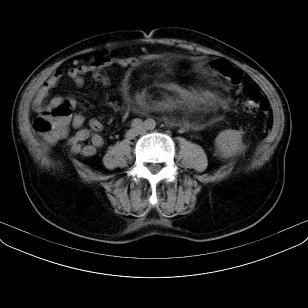

腹膜生占位性病变,脂肪肉瘤可能。

脂肪肉瘤,应测ct值。

考虑腹膜后脂肪肉瘤可能性大。 畸胎瘤不除外。